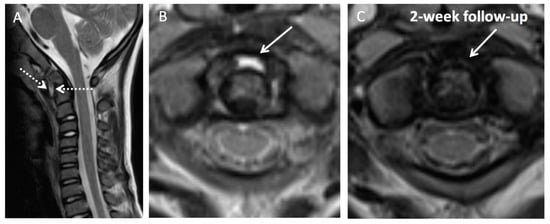

Illustration of Three Pediatric Cases of MRI in Inflammatory Nontraumatic Atlantoaxial Rotatory Subluxation